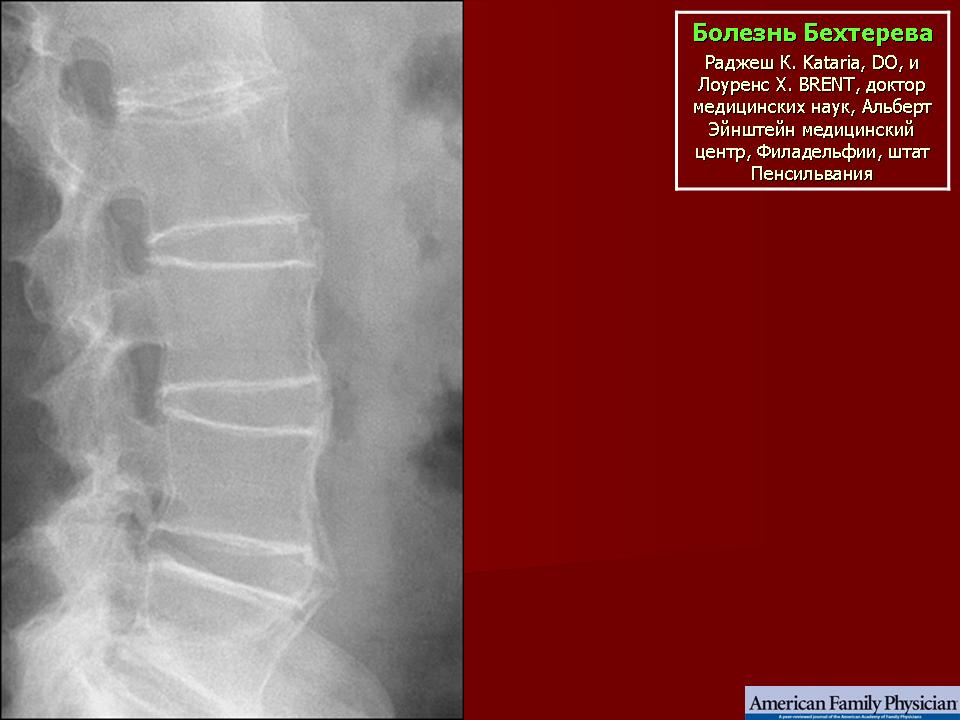

Болезнь Бехтерева

Поражение суставов при болезни Бехтерева

Болезнь Бехтерева — анкилозирующий спондилоартрит. Заболевание представляет собой воспаление межпозвонковых суставов, которое приводит к их анкилозу (сращению), из-за чего позвоночник оказывается как бы в жёстком футляре, ограничивающем движения. Преимущественно подвержены молодые мужчины, чаще 15-30 лет. Соотношение мужчин и женщин 9:1.

Во всем мире, в том числе и в России, еще 8-10 лет назад диагноз АС ставили в среднем через 7-8 лет от его начала. Это было в первую очередь связано с тем, что один из характерных и диагностически важных клинических признаков болезни — сакроилиит (воспаления крестцово-подвздошных суставов), можно было выявить только рентгенорафически. Однако этот признак мог проявится довольно поздно, через многие годы от начала болезни. В настоящее время возможно установить диагноз на ранней стадии с использованием МРТ крестцово-подвздошных суставов, который позволяет обнаружить активное воспаление КПС на ранних сроках. Рентгеновское исследование позвоночника на ранних стадиях имеет меньшее значение для постановки диагноза, но обязательно проводится для дальнейшего сравнительного анализа выявляемых изменений по мере прогрессирования болезни, а также для исключения возможных других причин болей в позвоночнике.

Диагноз подтверждается с помощью инструментальных и лабораторных методов диагностики. Рентген и МРТ в диагностике болезни Бехтерева используются как взаимодополняющие методы. Зачастую ультразвуковые исследования или МРТ кистей и стоп позволяют эффективно выявлять энтезиты (воспалительные поражения энтезов).

Инструментальные методы. Наиболее значимым тестом для установления диагноза анкилозирующего спондилита является выявление сакроилиита (воспаление крестцово-подвздошных сочленений). Сакроилиит выявляется при рентгенографии или магнитно-резонансной томографии (на ранних стадиях).

На рентгеновских снимках анклиоз становится заметен на второй стадии заболевания. Ранее увидеть проявления болезни можно с помощью МРТ. Однако этот вид обследования назначают редко.